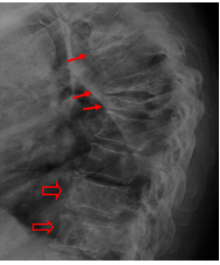

תפקידן של בדיקות הדמיה במיאלומה נפוצה

אילו בדיקות הדמיה קיימות במיאלומה? מתי משתמשים בכל בדיקה? מה ההבדל ביניהן? כל זה בכתבה מאת ד"ר תמיר שרגאי.